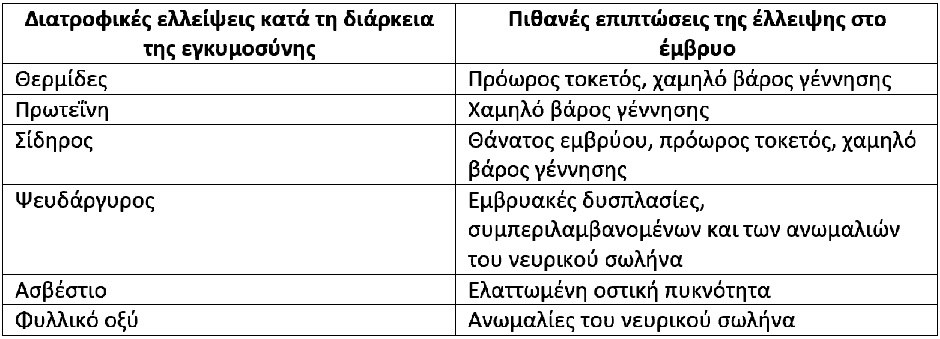

Εκτός από τα παραπάνω, υπάρχουν και άλλα απαραίτητα θρεπτικά συστατικά κατά την εγκυμοσύνη και η έλλειψή τους θέτει σε κίνδυνο την έκβαση της κύησης και την υγεία του νεογνού.

Στον παρακάτω πίνακα αναφέρονται μερικές τέτοιες περιπτώσεις.